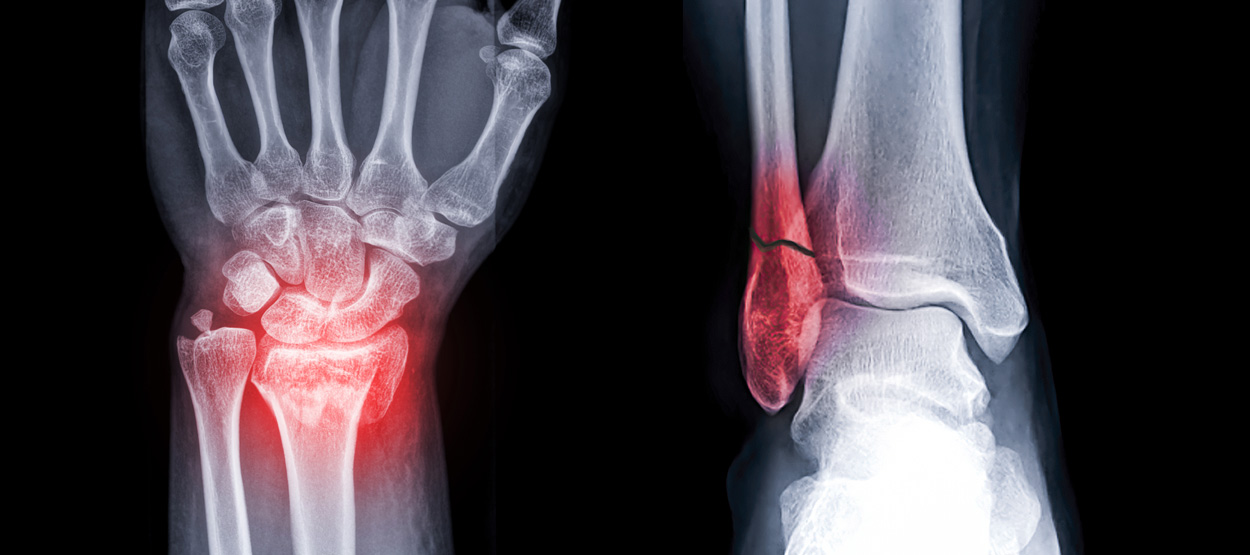

골절이 심하지 않은 경우에는 깁스로 고정해서 유합을 시킬 수 있으나, 정도가 심한 경우에는 손,발목 골절 수술을 진행할 수 있습니다.

골절은 정확하게 골절편을 잘 맞추고 고정하는 것이 중요합니다. 특히 관절면을 잘 맞추는 것이 중요합니다.

뼈에 금이 가거나 부러진 상태를 말합니다. 외부 충격, 낙상, 교통사고 등 다양한 원인으로 발생할 수 있으며,

모든 연령대에서 발생 가능하지만 특히 어린이와 노인에게서 흔하게 발생합니다.

손목 골절